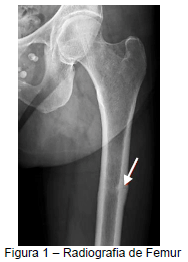

L.M.F, 60 anos, feminino, queixa dor persistente em quadril esquerdo de início há meses. Nega ter apresentado trauma local ou outros sintomas associados. Familiares sem histórico de fratura óssea, nega tabagismo, nega doenças associadas e nega uso prévio de corticoides. Relata que aos 50 anos realizou Densitometria Mineral Óssea sendo encontrado naquela ocasião: L1-L4: T Score -2,0. Fêmur total: T Score -1,7. Colo do fêmur: T Score -1,5. Devido a este exame, seu ginecologista iniciou alendronato 70mg uma vez por semana, medicação que vem em uso contínuo desde então. Você solicita nova densitometria óssea: L1-L4: T Score -1,5. Fêmur total: T Score -1,5. Colo do fêmur: T Score -1,5 e radiografia de fêmur (representada na Figura), cujo laudo apontava “reação de stress cortical com consequente espessamento, abaixo do trocanter menor”. Considerando o provável diagnóstico, assinale a conduta mais adequada neste contexto.